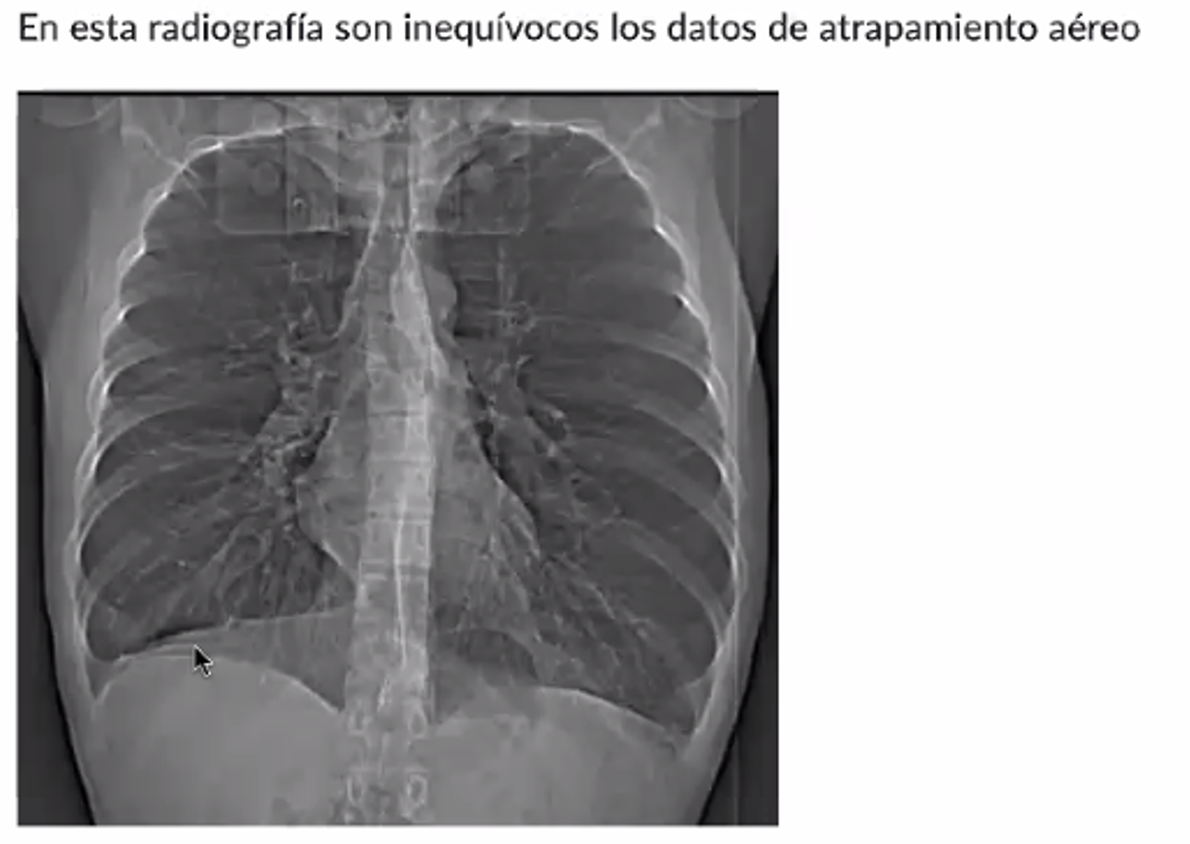

Hallazgos radiográficos: hemidiafragmas abatidos y aplanados, hiperluminosidad en ambos campos pulmonares con opacidades lineares bibasales y horizontalización de arcos costales, arco pulmonar abombado.

En base a los hallazgos clínicos, radiográficos y espirométricos el dx certero es

EPOC